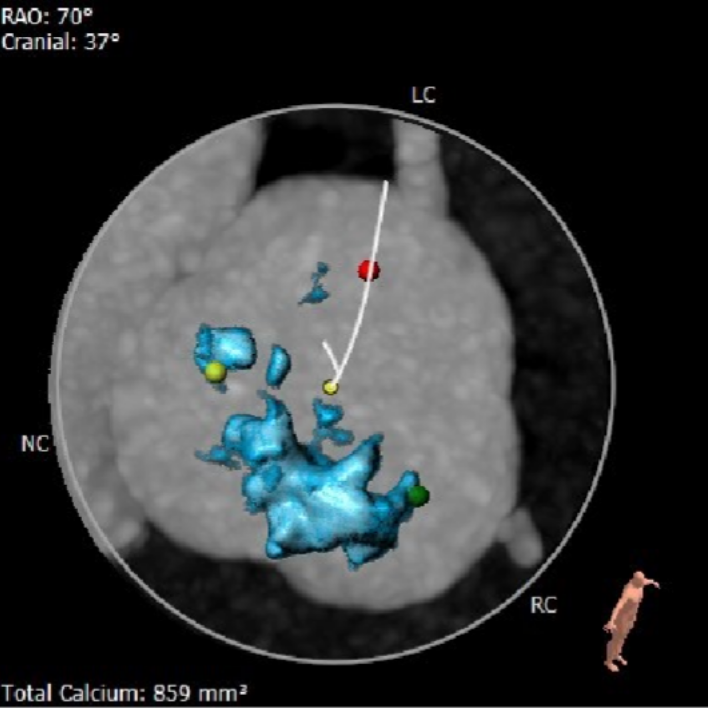

钙化分布

HU850钙化积分859mm³